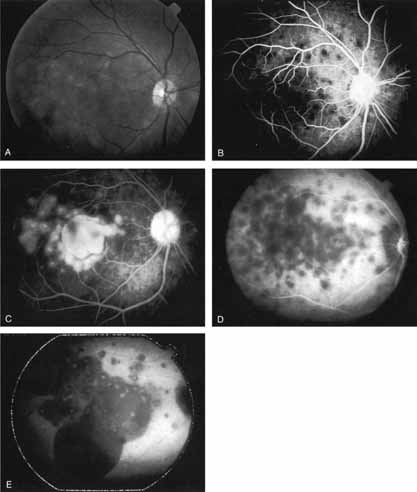

With this clinical diagnostic and histopathologic information available, pilot studies were performed to determine the practicality of using ICG angiographic guidance in the treatment of occult CNV. Slakter and associates28 performed laser photocoagulation treatment on 79 eyes with occult CNV. The occult CNV was successfully eliminated in 57% of patients who underwent ICG-guided treatment (Figs. 5 and 6). The authors found the success rate to be higher (66%) for patients with CNV not associated with PEDs than for those with PEDs (43%). Visual acuity improvement or stabilization was achieved in 57% of all patients. Recurrences were more frequent and more difficult to control in those patients who had associated PEDs on initial clinical presentation. Additional independent studies have reported similar diagnostic and treatment outcomes with the use of ICG angiography in patients with occult CNV.29,30

Sorenson and colleagues31 reported on the diagnostic and therapeutic ability of ICG angiography in patients who had clinical signs of recurrent CNV but who were found to have occult membranes on fluorescein angiography. In a group of 66 patients, 97% were identified as having localized areas of hyperfluorescence on ICG angiography consistent with recurrent CNV (Fig. 7). In laser photocoagulation treatment performed in a subgroup of 29 patients, 62% achieved anatomic resolution and stabilization of the exudative process over time. Visual acuity improved in 66%, 45% of whom achieved a visual acuity of 20/100 or better.